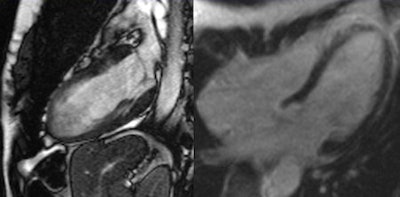

The major benefit of MRI is that it visualizes both the anatomy and the function of the heart in detail, and this makes it possible to detect conditions of the muscle as well as impaired wall motion and issues regarding oxygen supply or the pumping function. Emrich's team used cardiac MRI to examine 125 patients presenting with chest pain, elevated levels of troponin, and uncertain catheterization results. A diagnosis was established based on results from the MRI examination. A diagnosis based on the consensus of experts, including radiologists and integrating the subsequent clinical progression, served as a reference.

For 90% of these cases, cardiac MRI yielded the correct result, as was shown by a comparison with the reference diagnosis. Conditions associated with chest pain and elevated troponin levels include myocarditis, dilatative cardiomyopathy, Takotsubo cardiomyopathy, and hypertensive heart disease. In some cases, a myocardial infarction was shown that had not been detected by catheterization.